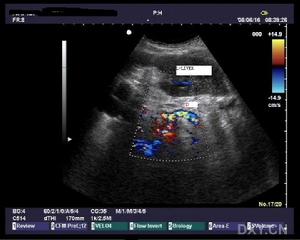

3.B型超声波检查虽然价廉无创,对胆囊结石的准确率达98%,但因受十二指肠等空腔脏器的影响,对胆总管结石的准确率仅为50%左右,特别对十二指肠后段胆管难以显示。假阳性及假阴性率均较高。 医学百科网 | YxBaike.Com